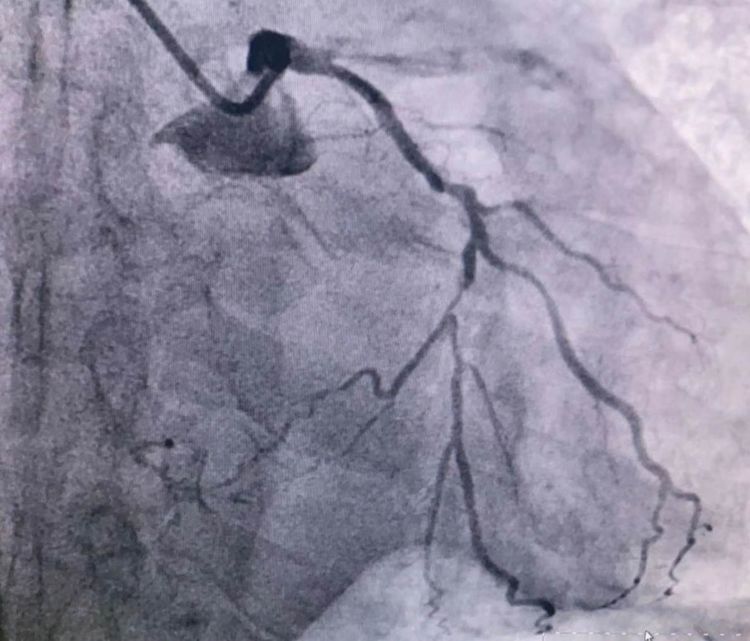

患者前降支、右冠100%閉塞,LCX中段60%狹窄。命懸一線,手術(shù)臺(tái)上持續(xù)胸痛。和患者家屬及時(shí)溝通后,決定行PTCA術(shù)。血壓低至60/40mmHg,在主動(dòng)脈內(nèi)球囊反博的支持下緊急行PCI術(shù)。軌道很快建立,導(dǎo)絲也及時(shí)通過(guò)病變血管,噩夢(mèng)來(lái)了,患者發(fā)生室顫了。在吳棟梁院長(zhǎng)的指揮下,李陽(yáng)主任和心臟團(tuán)隊(duì)的成員共同努力下,除顫、冠脈內(nèi)溶栓、多個(gè)球囊輪流上陣,患者病情平穩(wěn)了,罪犯血管及時(shí)開(kāi)通,血流恢復(fù)三級(jí)血流。平安下臺(tái),準(zhǔn)備擇日再處理冠脈情況。